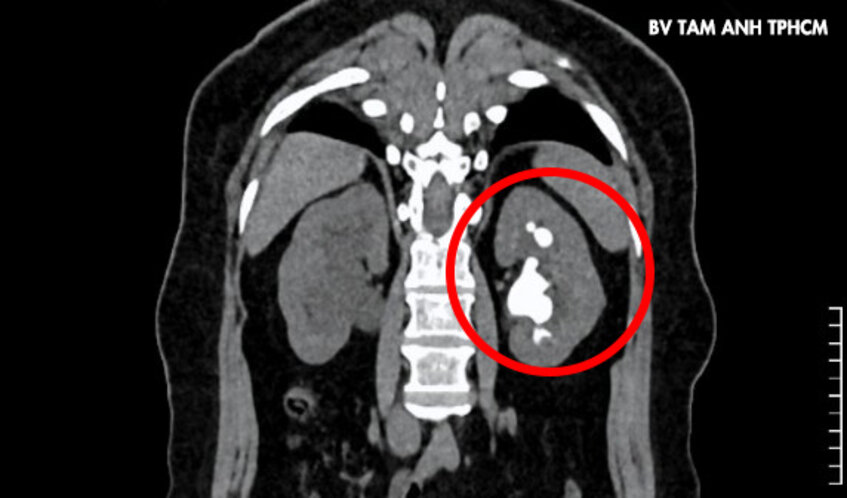

Lên cơn đau quặn thận, bà Trinh, 51 tuổi, ngụ TP.HCM đến Bệnh viện Đa khoa Tâm Anh TP.HCM khám, bác sĩ phát hiện người bệnh có sỏi cùng lúc ở đoạn trên niệu quản phải, kích thước khoảng 8×10 mm. Thận trái có sỏi kích thước 24×42 mm cùng nhiều sỏi nhỏ ở đài thận trên.

ThS.BS Nguyễn Tân Cương, Phó khoa Tiết niệu, Trung tâm Tiết niệu – Thận học – Nam khoa, cho biết sỏi thận trái có hình dạng san hô lấp đầy các đài thận, nguy cơ nhiễm khuẩn và tổn thương thận một cách âm thầm, người bệnh cần phẫu thuật sớm.

Sỏi san hô (còn gọi là sỏi struvite) là loại sỏi thận phức tạp và khó điều trị nhất trong các loại sỏi tiết niệu. Loại sỏi này có hình dạng giống nhánh san hô, chiếm gần như toàn bộ hệ thống đài – bể thận. Thành phần của sỏi thường là magie amoni photphat, hình thành chủ yếu do nhiễm trùng đường tiết niệu. Nếu không được điều trị kịp thời, sỏi san hô có thể gây ra các biến chứng nguy hiểm như nhiễm khuẩn, thận ứ nước, suy thận hoặc nhiễm khuẩn huyết.